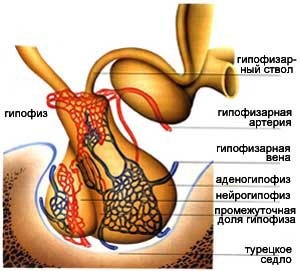

Fizic hipofiză sau inferior pridatok- cerebral este formarea în formă de boabe cântărind 0,5-0,6 grame, care este situat într-o cavitate a fundului craniului osos (buzunar os), numit șa turcesc.

Pituitară este format din trei părți: partea din față, din spate și intermediare. Toate aceste acțiuni sunt de fapt glande separate, fiecare secreta hormoni proprii.